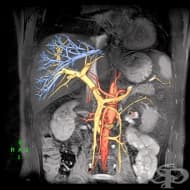

Флебография

Флебографията (от phlebos-вена и graphos-изобразявам) представлява рентгеново изследване на вените с...